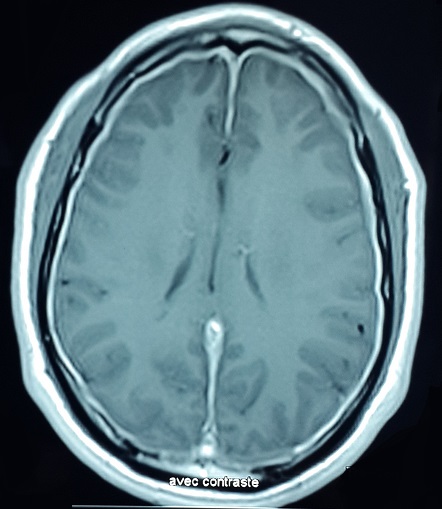

Les manifestations neurologiques centrales du syndrome de Gougerot-Sjögren primitif (SGS) sont très polymorphes, parmi lesquelles les pachyméningites représentent l'une des manifestations les plus rares, elles sont exceptionnellement révélatrices. Patient âgé de 40 ans présente depuis 7 ans des céphalées fronto-orbitaires gauches pulsatiles avec sono-photophobie. Depuis un an, les céphalées sont devenues plus intenses associées à une sécheresse oculaire et buccale. Une IRM cérébrale a objectivé une prise de contraste intense et épaissie des espaces méningés sous et sus-tentoriels réalisant l'aspet d'une pachyméningite diffuse. A l'examen clinique il n'y avait pas d'aphtose bipolaire ni d'érythème noueux ni de pseudo-follicules. L'examen de la sphère ORL était normal. La recherche de bacille de Koch dans les crachats ainsi que les sérologies syphilitique et de la maladie de Lyme étaient négatives. Le bilan phosphocalcique et le dosage de l'enzyme de conversion de l'angiotensine étaient normaux ainsi que la radiographie thoracique et la spirométrie. Le bilan immunologique (anticorps antinucléaires, ANCA) était négatif et l'étude du LCR était sans anomalies. Le test de Shirmer était pathologique et la biopsie des glandes salivaires était en faveur d'une sialadinite stade IV de Chisholm confirmant le diagnostic du SGS. Les causes des pachyméningites sont très diverses: infectieuses, inflammatoires, médicamenteuses, néoplasiques ou idiopathiques. Bien que la survenue d'une pachyméningite dans un contexte de SGS soit exceptionnelle, un tel syndrome doit être évoqué dans le cadre du bilan étiologique d'une pachyméningite.